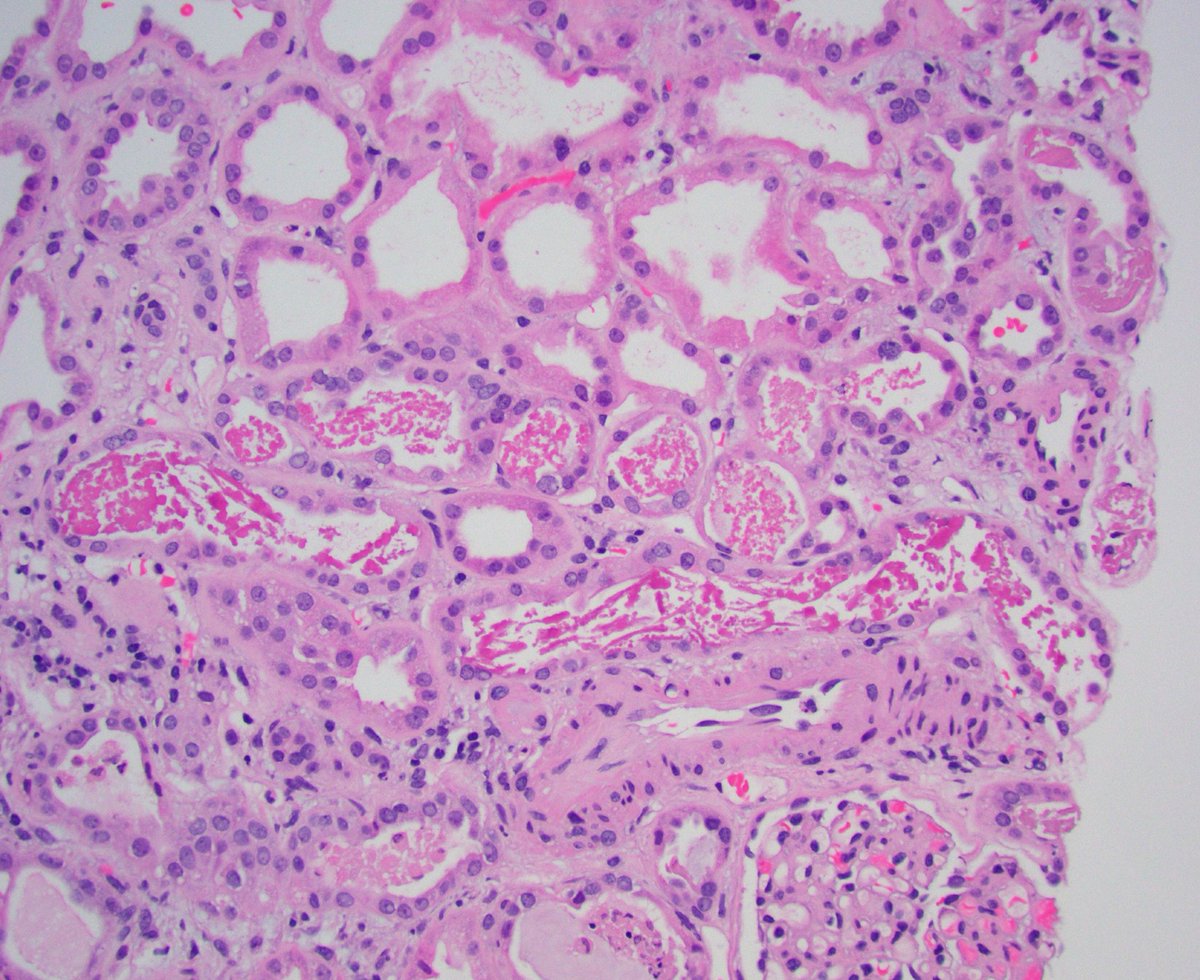

Kidney txp biopsy for AKI (~6 post txp). Tubular injury associated with granular and ropey trichome positive casts. IHC confirmed myoglobin cast nephropathy. CK found to be very high; thought to be due to statin related myopathy. #renalpath #pathwitter #nephrology

1

18

57